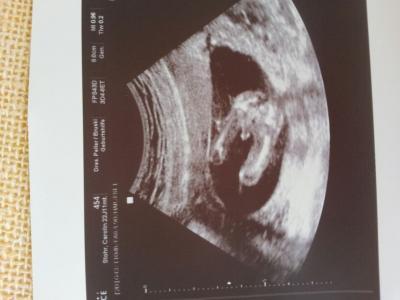

hallo ihr lieben . habe einen sehr ausgiebigen ultraschall gehabt ( klar bezahlt ) und nun wissen wir es wird sicher ein JUNGE .. oh man habe mir sooo ein mädchen gewünscht aber was solls . war einfach glücklich das alles dranist und kern gesund :) und sooo süß hat mit seinen beinen gespielt . mit seinen händen festgehalten so süß und total am zappeln . ist kanpp 10 cm groß

achja auf dem ersten bild direkt zwischen den beinen ;) hier einmal von schäh oben das händchen